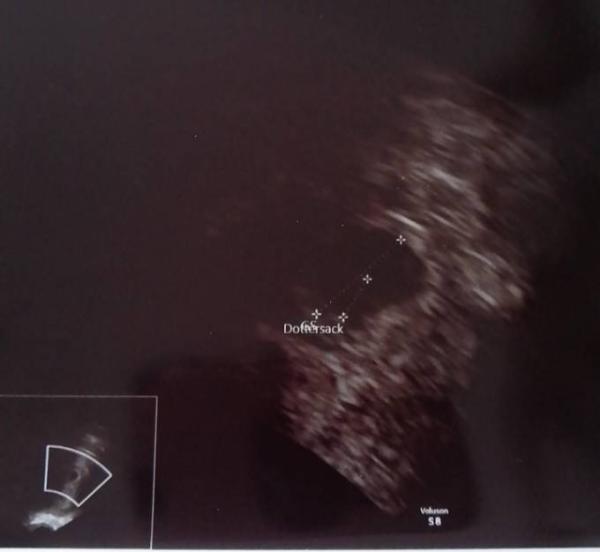

Heute war ich wieder beim Frauenarzt zur Kontrolle. Da hatte man den Dottersack gesehen. Das Baby muss sich wohl versteckt haben

Bild zu 5+5 - Forum für Juli - Mamis